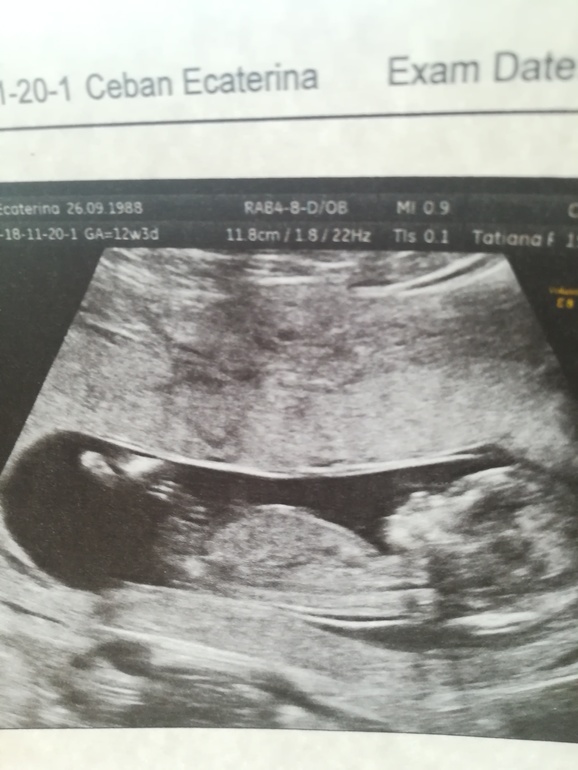

Привет девочки !) вот и я прошла 1 скрининг , конечно волновалась очень, но всё же прошло хорошо, когда врач говорил про нашу лялечку, про строения, ораны я потихоньку выдыхала )

В итоге все в норме, чсс 172 уд. Срок 11,5

Холила с мужем , врач все ему показал рассказал ( делали в жк, бесплатно ) , у нас первый сынок и я конечно мечтала и думала что будет девочка, но когда врач приблизила и показала на бугорок, говорит на таком сроке рано конечно, но предположительно мальчик ) конечно я уже люблю и мальчика, главное чтобы здоровенький , но еще малюсенькая надежда на девочку у меня остается, ну прям очень дочу хочется ) интересно у кого то на таком сроке ошибались с предположением? спасибо кто прочитал 😊 фото моей крошки )